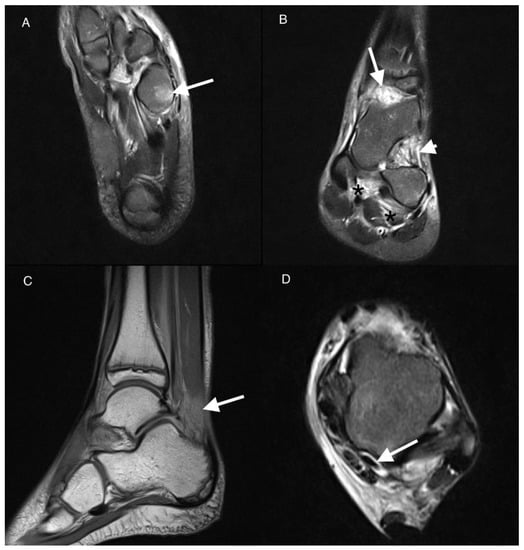

| 0 | 16 (73%) | 22 (100%) | 0.031 | |

| 1 | 4 (18%) | 0 (0%) | ||

| 2 | 2 (9%) | 0 (0%) | ||